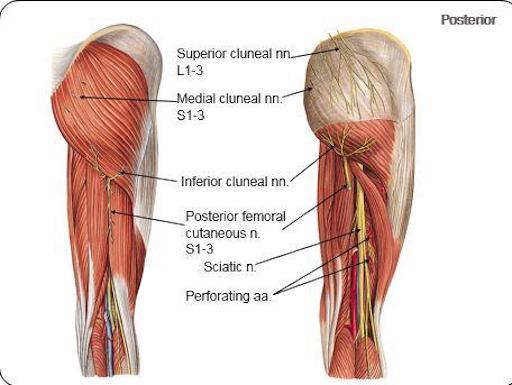

origin and course of superior cluneal nerve

posterior rami of L1-L3 nerves

crosses iliac crest

name the clunial nerves and their distribution

spinal cord levels

superior (posterior rami of L1-L3), inferior (S2-S3) and middle clunial nerves (posterior rami of (S1-S3)

supplies the skin of the gluteal region as far as greater trochanter

origin and course of middle clunial nerve

posterior rami of S1-S3 nerves

exits through posterior sacral foramina and enters gluteal region

origin and course of inferior clunial nerve

posterior cutaneous nerve of thigh

curves around inferior border of gluteus maximus

origin course and distribution of posterior cutaneous nerve of the thigh

O S1-S3

C From pelvis below piriformis, beneath gluteus maxius and back of thigh, bakc of knee and dives into deep fasica and runs with small saph to middle of back of leg. gives off inferior clunial n.

D posterior surface of thigh and leg, skin of perineum